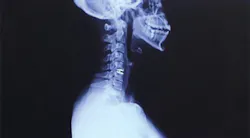

A herniated disk was the cause of years of pain resulting from improper workplace ergonomics

While it did take some time, a neurologist finally confirmed that a herniated disk in my neck was the cause of my pain. I was initially prescribed one month of physical therapy, which eventually turned into three. The co-pays and the unpaid sick time I needed to take away from the office added up to approximately $5,000. Unfortunately, physical therapy was only a short-term fix, and the herniated disk continued to wreak havoc on my life.

Seeing the scar on my neck, resulting from the subsequent cervical disk replacement surgery, patients were more willing to lie back farther and turn toward me when I asked. I frequently ask myself if surgery could have been avoided if I had advocated for myself and required my patients to accommodate me. If I had invested in my loupes and my saddle stool earlier, could that have helped?